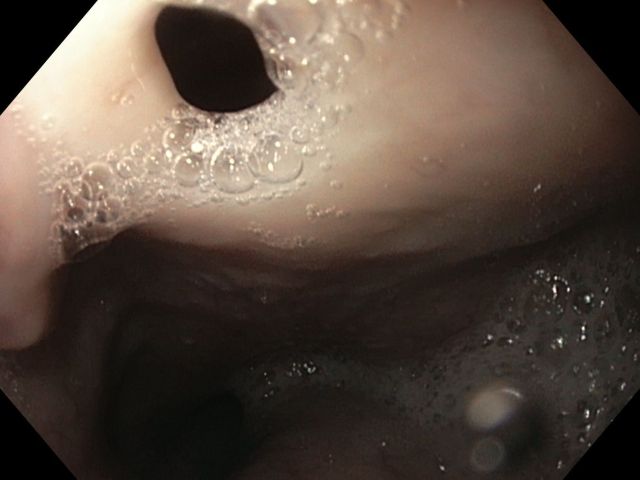

Refractory tracheoesophageal fistula management with Amplatzer Occluder placement

Menção Honrosa - Fotografia